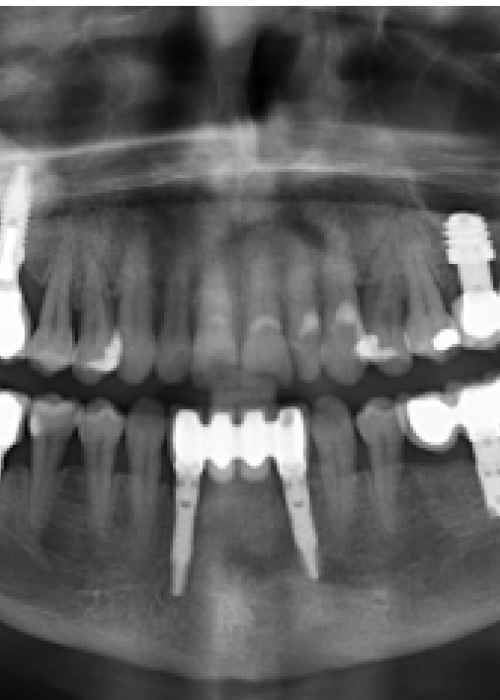

Implantes de 4,5mm de longitud utilizados en atrofia ósea en altura (hueso residual ≤ 4,5m). Estudio retrospectivo

Elevación de seno mediante abordaje transcrestal sin material de relleno con implantes extracortos (5,5 y 6,5 mm). Estudio retrospectivo con un seguimiento de 10 años

Elevación de seno transcrestal con inserción de implantes ultracortos de 4,5 mm de longitud en zonas maxilares posteriores con hueso residual menor o igual a 3 mm de altura

Implantes de 4,5 y 5,5 mm longitud insertados de forma directa en elevación crestal con hueso autólogo unido al Endoret-PRGF en alturas óseas residuales de 2-3 mm: estudio retrospectivo